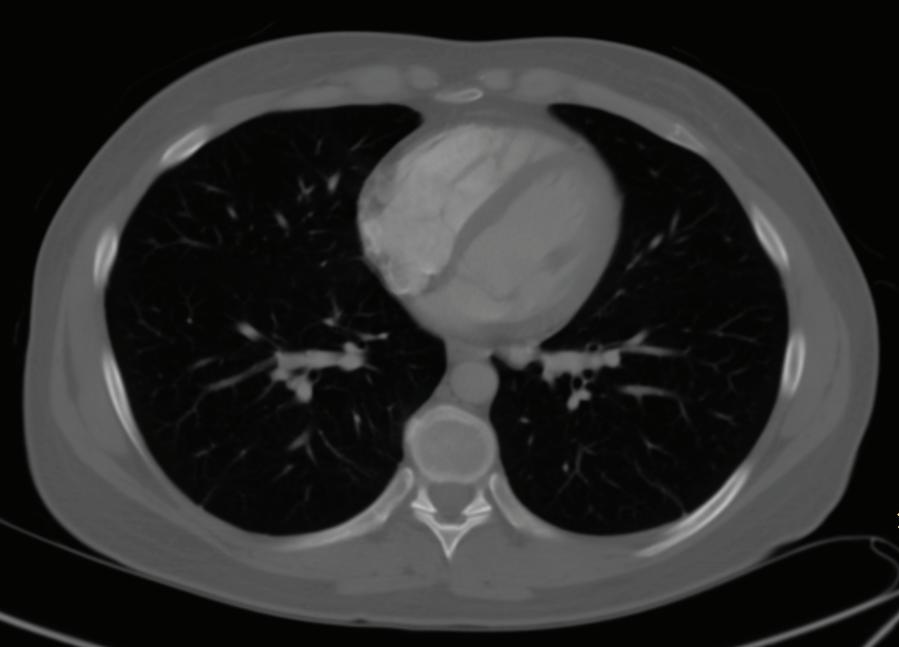

FIGURE 1-20 Three axial chest CT images using different window settings. The top image was made using a soft tissue window. In this image, the different soft tissue densities (note: muscles and intermuscular fat planes) and the bright contrast enhancement of blood in the heart are very conspicuous. The middle image was made using a lung window setting, in which lung markings, mainly pulmonary veins, are visible. The lower image was made using a bone window setting. With these window and level settings, you can see the distinction between marrow and cortical bone in the ribs.